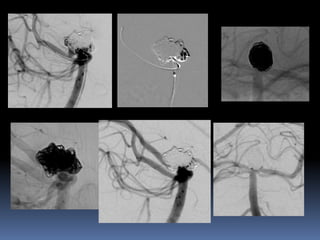

•Retrospective review of 548intracranial aneurysms

•35 aneurysms in 33 patients -F-19, M-14; 30-68 yrs

•Fisher grade III SAH -22 (66.6%)

•H& H grade-I-III -27 (81.8%)

•EVD/ Lumbar drainage-8 (24.2%)

•<14 days of SAH-26(78.7%)

•Wide Neck aneurysms -16

•Dissecting and/or blister aneurysms-19

•Single (28) or double overlapping (5) stents with additional coil placement in 26 aneurysms.